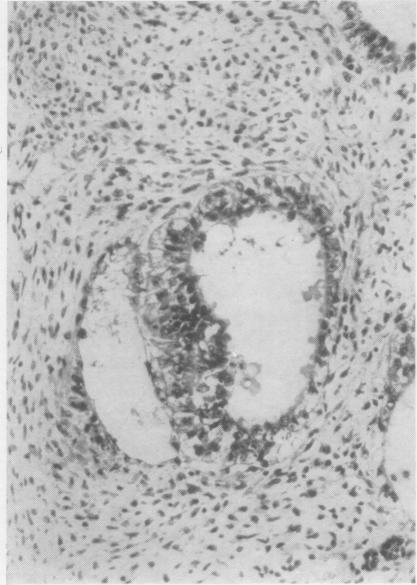

Developmental stages of embryo-like bodies in teratoma testis.